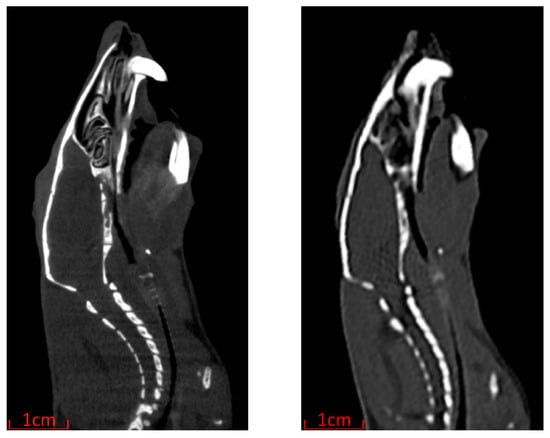

The greatly reduced time per scan and maximum patient size of the Siemens SOMATOM go.Up come at the cost of decreased spatial resolution compared with the Inveon Multimodality System as highlighted in Figure 4. Despite the decreased resolution, as the tumour volume and skeletal landmarks are easily identifiable, the Siemens SOMATOM go.Up was the scanner chosen for image-guided MRT in this work.

Figure 4. Sagittal reconstruction of rat comparing CT scan image quality. Inveon Multimodality System with 97 μm × 97 μm × 97 μm voxel resolution (left) and Siemens SOMATOM go.Up with 300 μm × 300 μm × 300 μm voxel resolution (right).